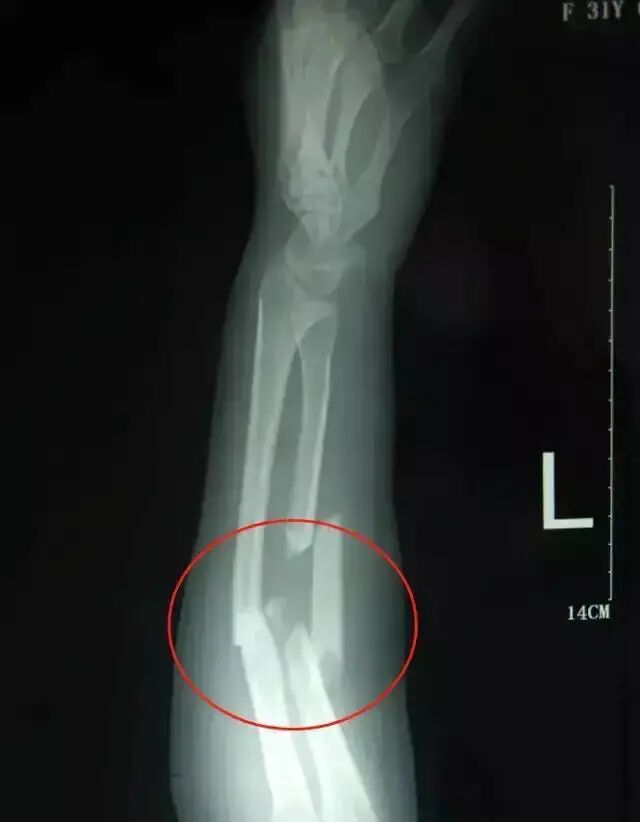

(吴菊萍胳膊受伤拍片)

但片子显示,吴菊萍左手臂的尺桡多段粉碎性骨折,伤势非常严重。

医生建议直接到专业的骨科医院。

会诊后,金登峰发现,吴菊萍的伤势是他见过的尺桡骨骨折中,伤得最严重的。

但是他说,从没见过这么严重的爆裂伤,以前像这种伤只在严重的车祸中见过。

他总结,吴菊萍这个伸手接人的举动非常危险,她是在拿自己的命救人。

一位网友在听说了吴菊萍的事迹后,用自己所学的公式去估算当时吴菊萍在接小女孩的一瞬间,她的手臂到底承受了多重的重量。

他假设这个2岁孩子重30斤,从10层楼的高度坠落,吴菊萍接住她时的重量,相当于用手接住了一个335.4公斤的物体!

但实际上,一般人的手臂所能承受的重量只有45公斤左右,而吴菊萍却瞬间接住了一个超过常规标准近8倍的重物。